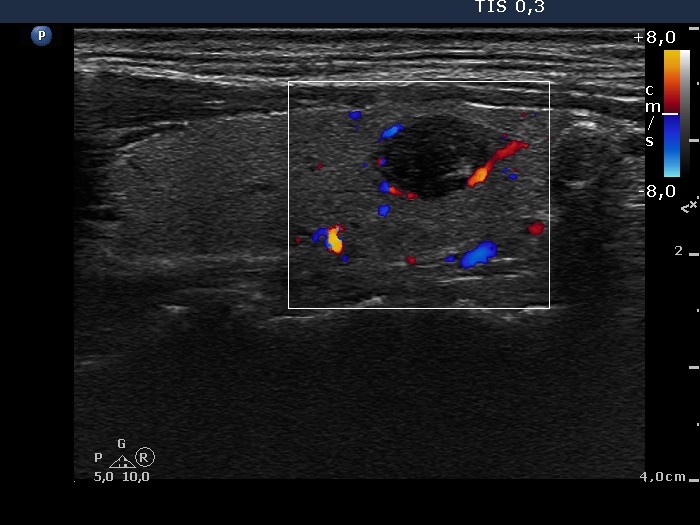

100 consecutive cases of papillary cancer - case 034 (ultrasonographic picture 7)

Left lobe, longitudinal scan, color Doppler mode. The papillary carcinoma focus presents signs of perinodular blood flow.